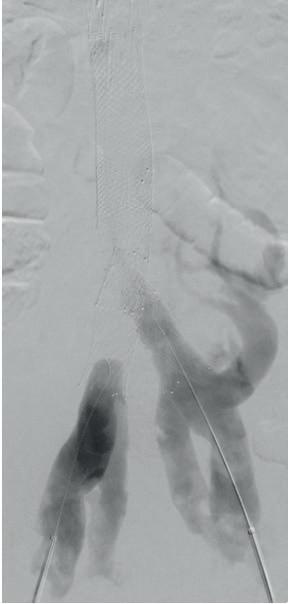

A NOVEL PHYSICIAN-MODIFIED ENDOGRAFT (PMEG) technique for the treatment of thoracoabdominal and complex abdominal aortic aneurysms (TAAA and AAA) involving delayed-release diameter reduction to aortic size and shape—allowing for sequential target vessel cannulation—is safe and effective, according to a new study.

Results from the 203-patient analysis of PMEG fenestrated endovascular aneurysm repairs (FEVARs)—carried out in a physician-sponsored investigational device exemption (PS-IDE) at Dartmouth Hitchcock Medical Center in Lebanon, New Hampshire, from 2017–2024—were presented at the 2025 annual meeting of the New England Society for Vascular Surgery (NESVS) in Providence, Rhode Island (Sept. 26–28). Delivering the data, Kirthi Bellamkonda, MD,

a vascular surgery resident at Dartmouth Hitchcock, set the scene: despite the emergence of commercial devices into the complex aortic aneurysm repair space, PMEG remains the predominant technology to treat these patients, and the traditional PMEG technique has changed little since its inception. Bellamkonda reported an average aneurysm diameter of 59.9mm among the cohort, with a distribution of 24% juxtarenal aneurysms, 46% pararenal aneurysms, 10% extent IV TAAAs and 18% extent II or III TAAAs. Technical success was 100%, with 30-day outcomes showing 2.5% mortality, 2% organ failure (of which half was renal failure), about 1% paraplegia and paraparesis, and 5% access site complications.

At one year, there were no cases of open conversion, stent fracture or migration, Bellamkonda added. Paraplegia and

paraparesis were found to be similar to the 30-day outcomes. One-year target vessel instability was 6.6%, of which 2% was component stenosis and 4.6% component occlusion. So why delayed-release diameter reduction, Bellamkonda pondered. “We reduce the number of simultaneous wires from four to one compared to the traditional technique, which reduces the risk of wire loss and re-cannulation, as well as the trauma to bridge vessels,” she said. “This allows us to work with a smaller contralateral sheath and improves intraoperative efficiency.” Given the continued role for PMEG in complex treatment, Bellamkonda said that the study group hopes to see the technique and design disseminate and help inform industry improvements in graft manufacturing. Bryan Kay

A series of images shows cannulation of